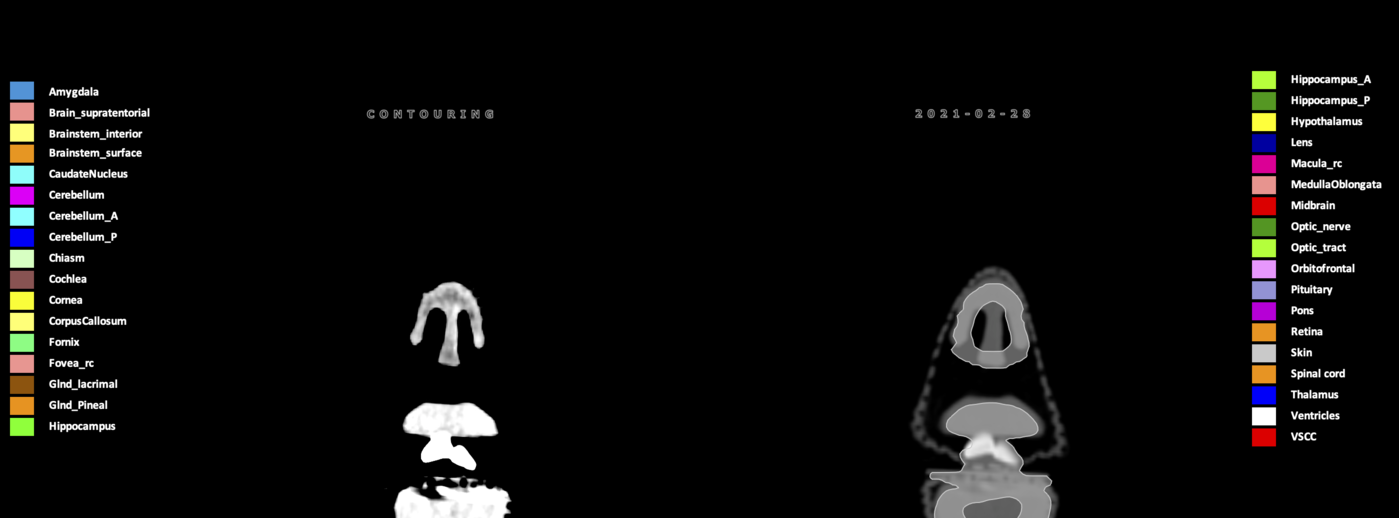

Included are all OARs known to be relevant for radiation-induced toxicity in neuro-oncology: brain, brainstem (midbrain, pons, medulla oblongata), chiasm, cerebellum (anterior & posterior), cochlea, cornea, hippocampus (anterior & posterior), hypothalamus, lens, lacrimal gland, optic nerve, pituitary, skin, and vestibular & semicircular canals. To further facilitate research on cognition, vision and radiological changes after irradiation of the brain, potential clinically-relevant OARs are included: amygdala, caudate nucleus, cerebellum (anterior & posterior), corpus callosum, fornix, macula, optic tract, orbitofrontal cortex, periventricular space (PVS), pineal gland, and thalamus.

Three-dimensional delineation of the 25 consensus OARs for neuro-oncology are shown on CT (WW/WL 120/40, 3000/600), 3T MR images, (T1Gd, T2FLAIR 1mm) and 7T MR (MP2RAGE 0.7 mm). All are presented in transversal, sagittal and coronal view.